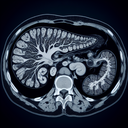

МРТ органів черевної порожнини

Магнітно-резонансна томографія (МРТ) органів черевної порожнини — це неінвазивний діагностичний метод, що використовує сильні магнітні поля та радіохвилі для створення детальних зображень внутрішніх структур. ### Що досліджує МРТ черевної порожнини: - Печінка та жовчний міхур - Підшлункова залоза - Нирки і наднирники - Селезінка - Кишківник - Судини черевної порожнини - Лімфатичні вузли та інші тканини ### Показання для проведення: - Біль у животі незрозумілого походження - Оцінка пухлин (розмір, форма, поширення) - Діагностика захворювань печінки (цироз, гепатити) - Патології жовчного міхура (камені, запалення) - Оцінка поширення раку - Пошук запальних процесів або інфекцій - Аномалії судин черевної порожнини ### Переваги МРТ: - Висока роздільна здатність зображень - Немає використання іонізуючого випромінювання (як у КТ) - Можливість оцінки м'яких тканин ### Підготовка до процедури: - Інколи потрібне утримання від їжі за 4-6 годин до процедури - Необхідно повідомити про металеві імпланти чи інші протипоказання - Одягнути зручний одяг без металевих деталей ### Протипоказання: - Наявність кардіостимулятора або металевих імплантів - Клаустрофобія (в деяких випадках) ### Що варто мати на увазі: - Обстеження триває зазвичай від 30 хвилин до години - Під час процедури необхідно лежати нерухомо Якщо у вас є конкретні питання або сумніви, краще звернутися до лікаря, який зможе надати рекомендації та пояснити, чи потрібно робити цю діагностику у вашому випадку...